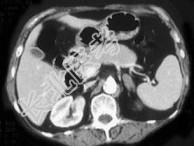

- 单项选择题女,42岁, 夜尿增多伴高血压,实验室检查: 血和尿醛固酮水平增加,请结合图像, 选择最佳答案 ( )

A、双侧肾上腺增生

B、双侧肾上腺腺瘤

C、双侧肾上腺未见异常

D、双侧肾上腺转移瘤

E、双侧肾上腺淋巴瘤